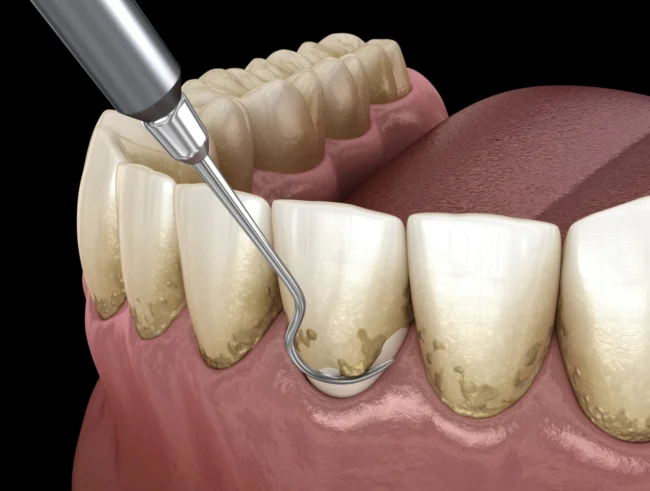

Raspado y alisado radicular: qué es y cómo saber si lo necesito

Es muy común que muchos pacientes acudan a nuestra clínica dental en Madrid, en la calle San Bernardo, solicitando una «limpieza bucal normal» y, tras una exploración detallada por nuestros odontólogos, descubramos que necesitan un tratamiento más profundo para eliminar los restos de placa y devolver la salud a sus dientes y encías. Es en…